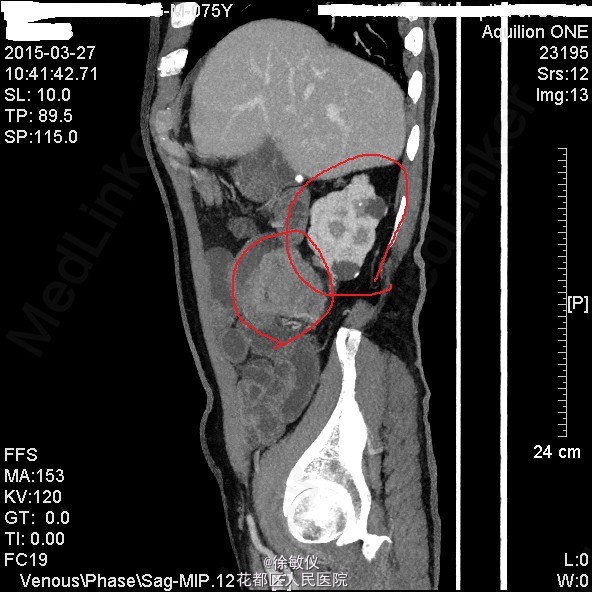

查体:生命体征平稳,贫血面容。腹软,全腹无压痛、反跳痛,右中腹可触及一大小约4*5cm包块,边界清晰,质稍硬。肝脾肋下未触及。 辅查:HGB 82g/L;CA19-9 625.97U/ml;CA-125 24.9U/ml;大便常规示:粪血红蛋白试验阳性。 全腹CT平扫+增强示:1、结肠肝曲及升结肠癌,浸润肠壁全层,周围多发淋巴结转移;2、直肠多发小息肉;直肠下段静脉曲张。